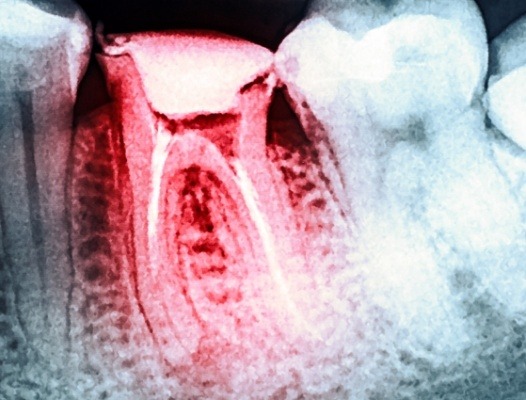

X-ray of smile after root canal therapy

There are people who do not experience any symptoms when they have an infected tooth. That is why regular dental checkups and annual digital X-rays are so important. In addition, these visits can help you avoid tooth infection with professional cleanings and examinations that spot decay early before a cavity has the chance to spread.

Meeting with an emergency dentist in Phoenix requires a thorough examination of your oral anatomy. We will not only visually evaluate your problem tooth, but we will also capture digital X-rays to receive a complete view. Once we review our findings, we will incorporate the following factors into your cost estimate: